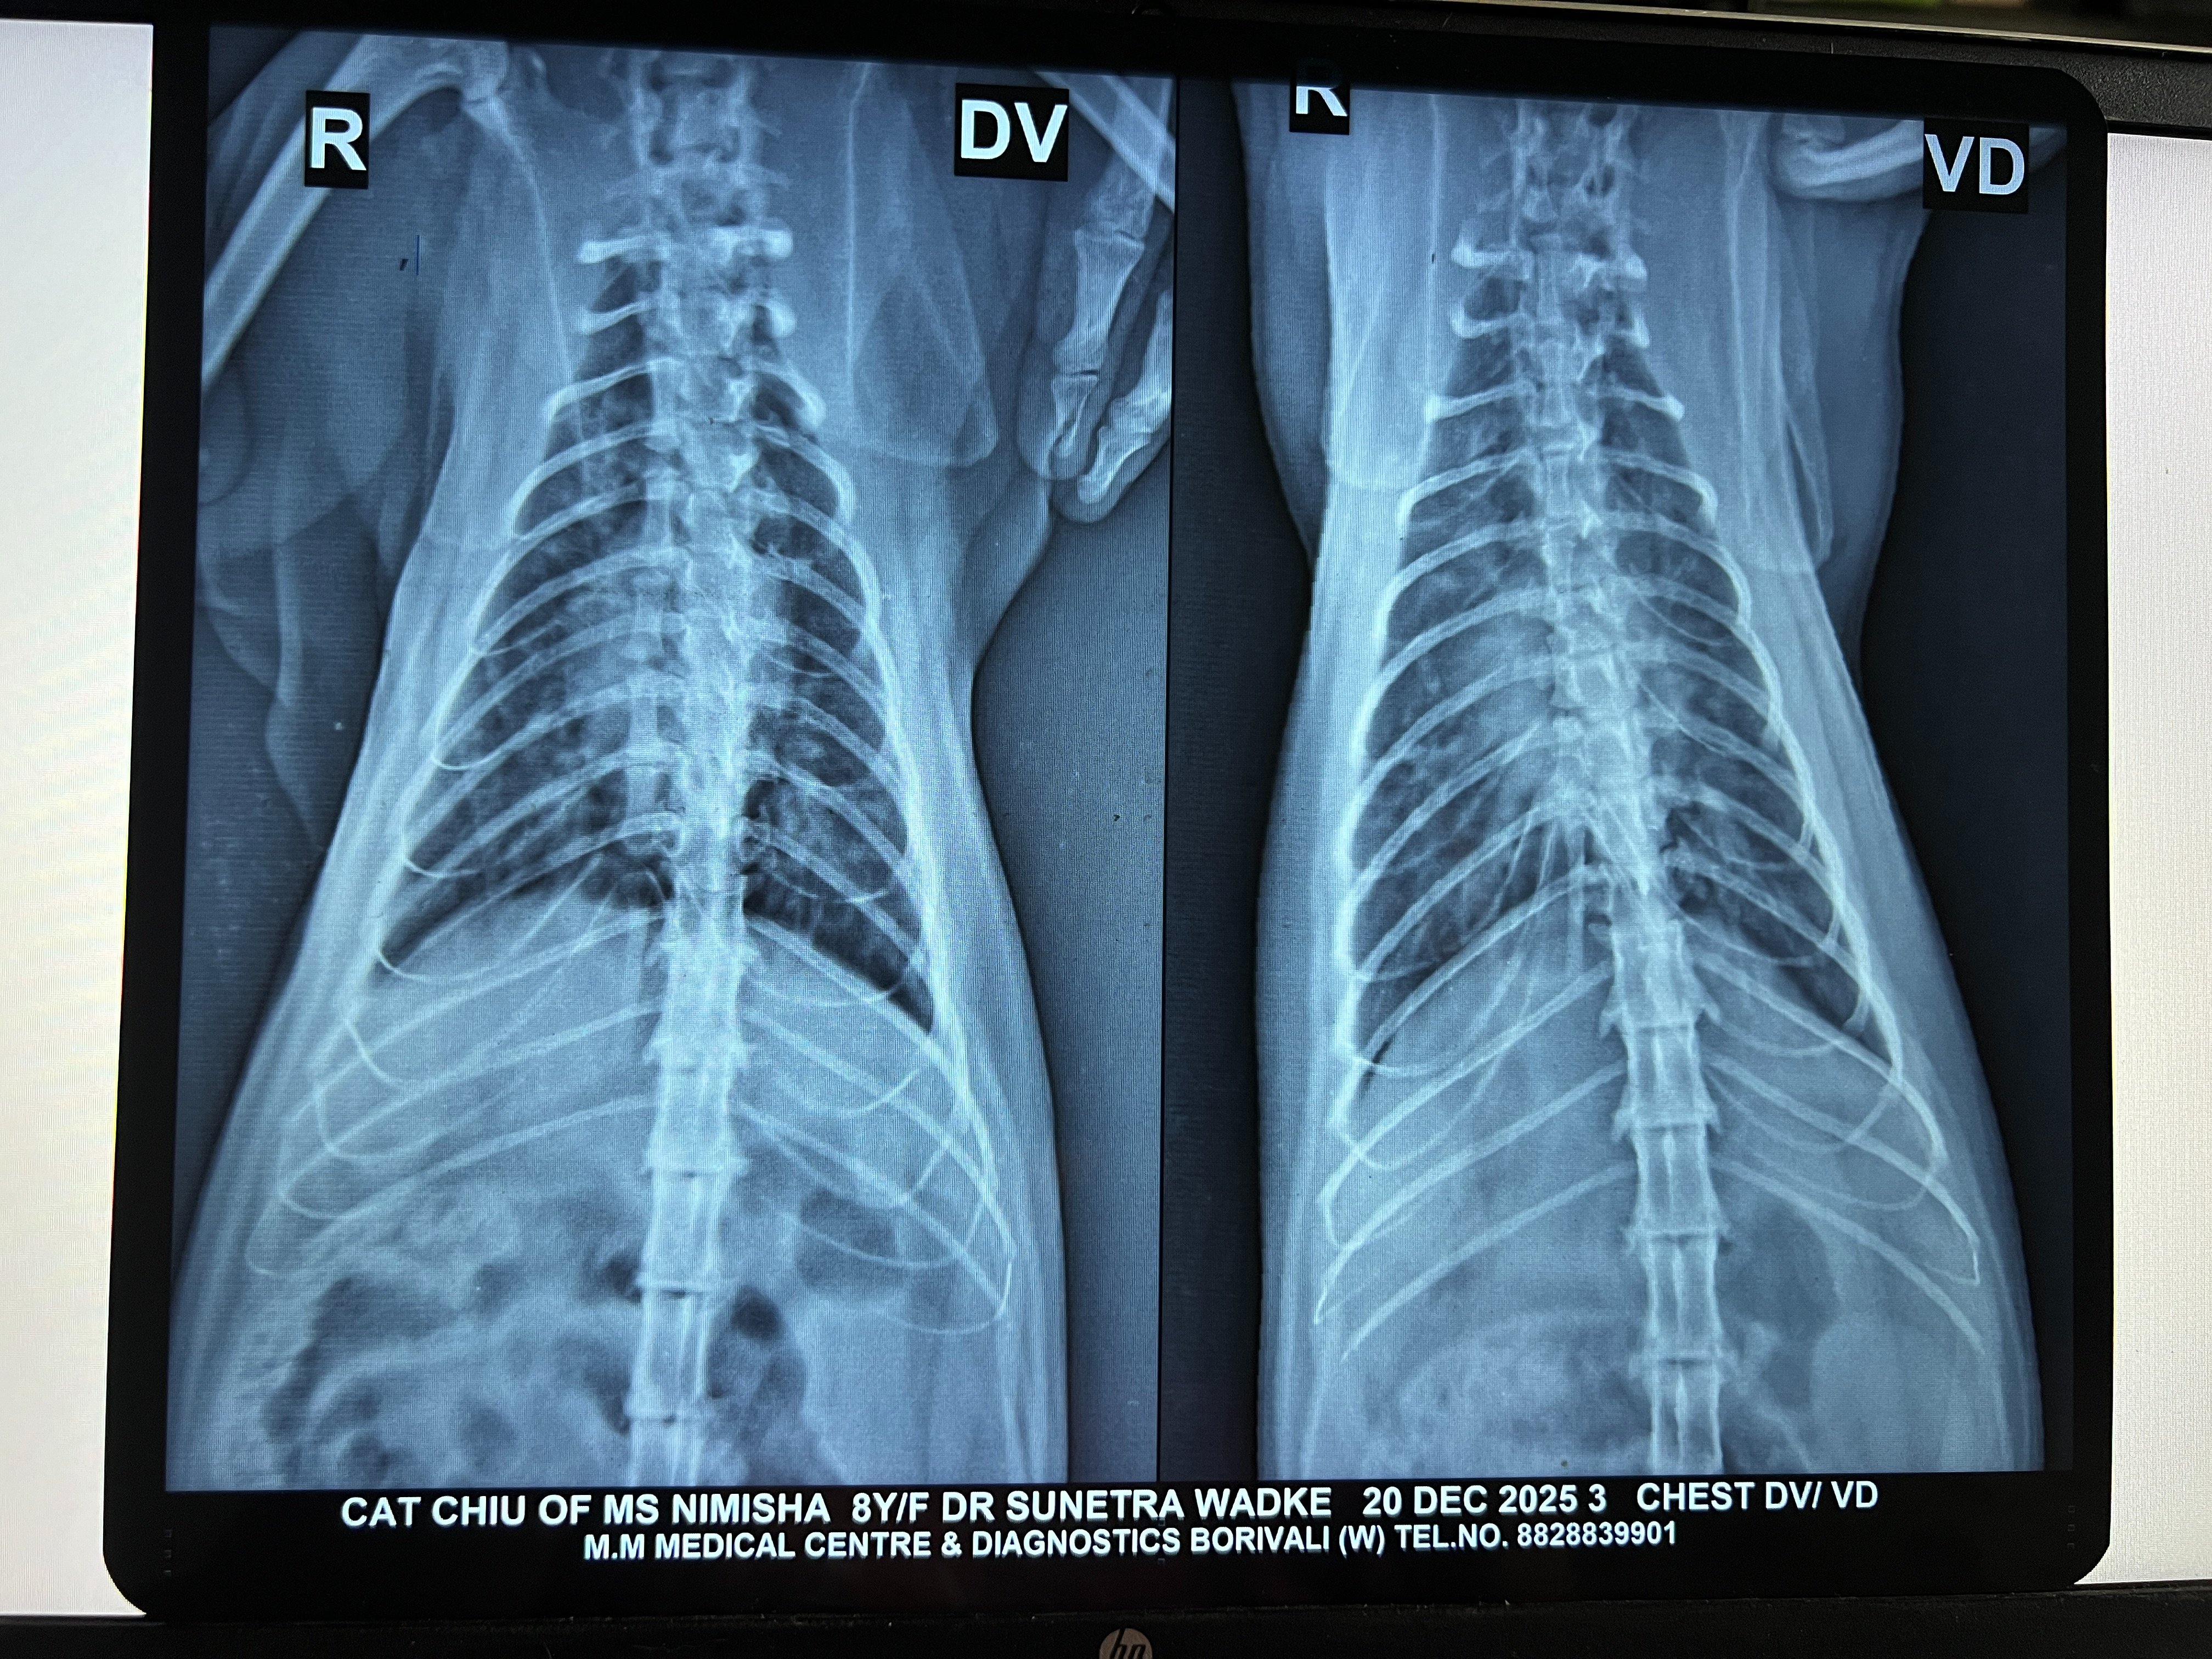

Yesterday was the x-ray which still showed congestion. We did a 2d echo (scans attached). Vet said stuff like HCM, regurgitation, dilation. I had briefly read about HCM and got overwhelmed and didn't ask the vet for more details. But she sent me off with 30 days medicines (long list of meds below) and we'll do a repeat 2d echo after a month. ETA: she lost about 0.5 kg in the last 15 days.

I'm attaching her labs (Mar/Jul/Sep), x-rays (Aug/Sep/Nov/Dec) and 2d-echo (Dec).

4.2 Xray - DV VD - Chiu - 20Dec2025.jpeg2.4 MB · Views: 41 -